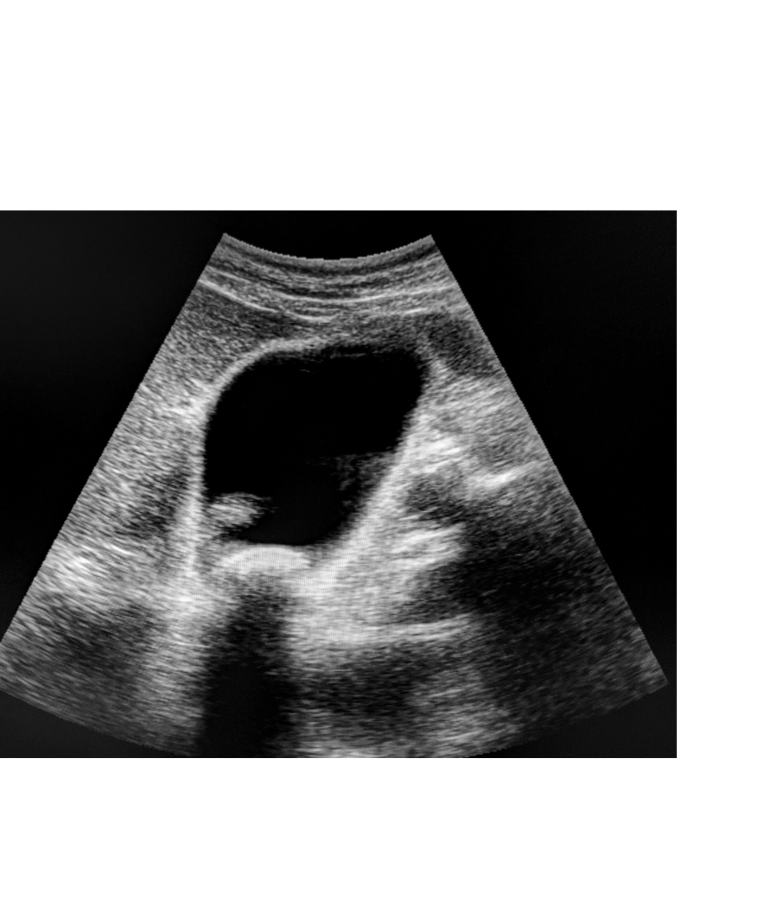

Ecografia addominale: è il metodo diagnostico di prima scelta per visualizzare i calcoli all'interno della colecisti. È non invasiva, veloce ed efficace.